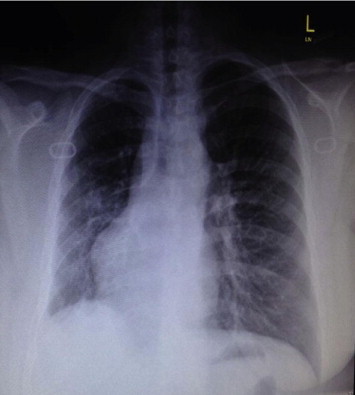

Figure 1.

Chest X-ray of the chest showing possible dextrocardia.

A 49-year-old female presented with pneumonia. On examination, heart sounds were heard on the right side of the chest, resulting in an initial impression of dextrocardia. Chest X-ray (Fig. 1) and echocardiography demonstrated dextro-position of the heart with no associated congenital anomalies. Subsequently, computed tomography of the chest was performed, revealing an absence of a right lung parenchyma with abrupt termination of right main bronchus after bifurcation of the carina, and a shift of the heart to the right side as shown in Fig. 2. No other congenital anomalies were detected.